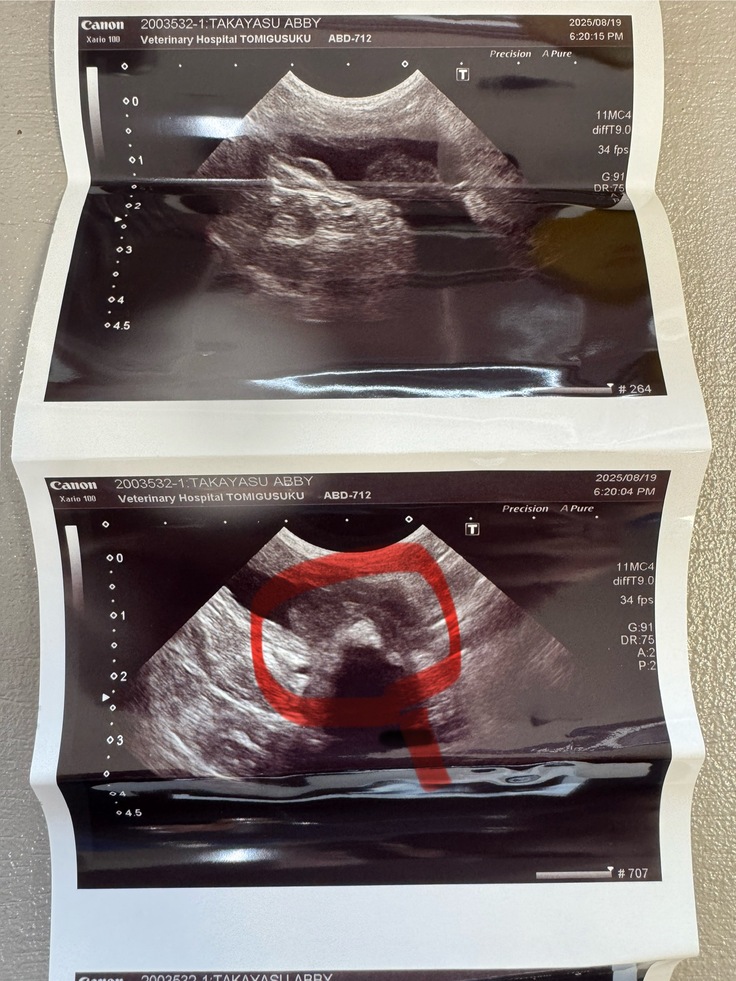

8/19にアビの調子が悪く、受診致しました。

排尿の量が少なくなってたので検査してもらいましたが、原因は膀胱に腫瘍が出来ていました。以前のエコーではわからなかったんですが、それが原因で排尿時に鳴いてたようです。

手術するにはCT撮って、手術なのですが、どちらも麻酔をかけておこなうとのことでアビの身体が持つのかというリスクがあるようです。

赤く囲ってある白が濃くなってる部分が腫瘍のようです。

今は消炎剤を飲んで少し落ち着いており、排尿も量が少ないですが頻回なので膀胱には溜まってないので安心しました。鳴き声も以前よりは小さく痛みも軽減されているようです。

敢えてリスクを取るより、今の現状を選ばさせていただきました。